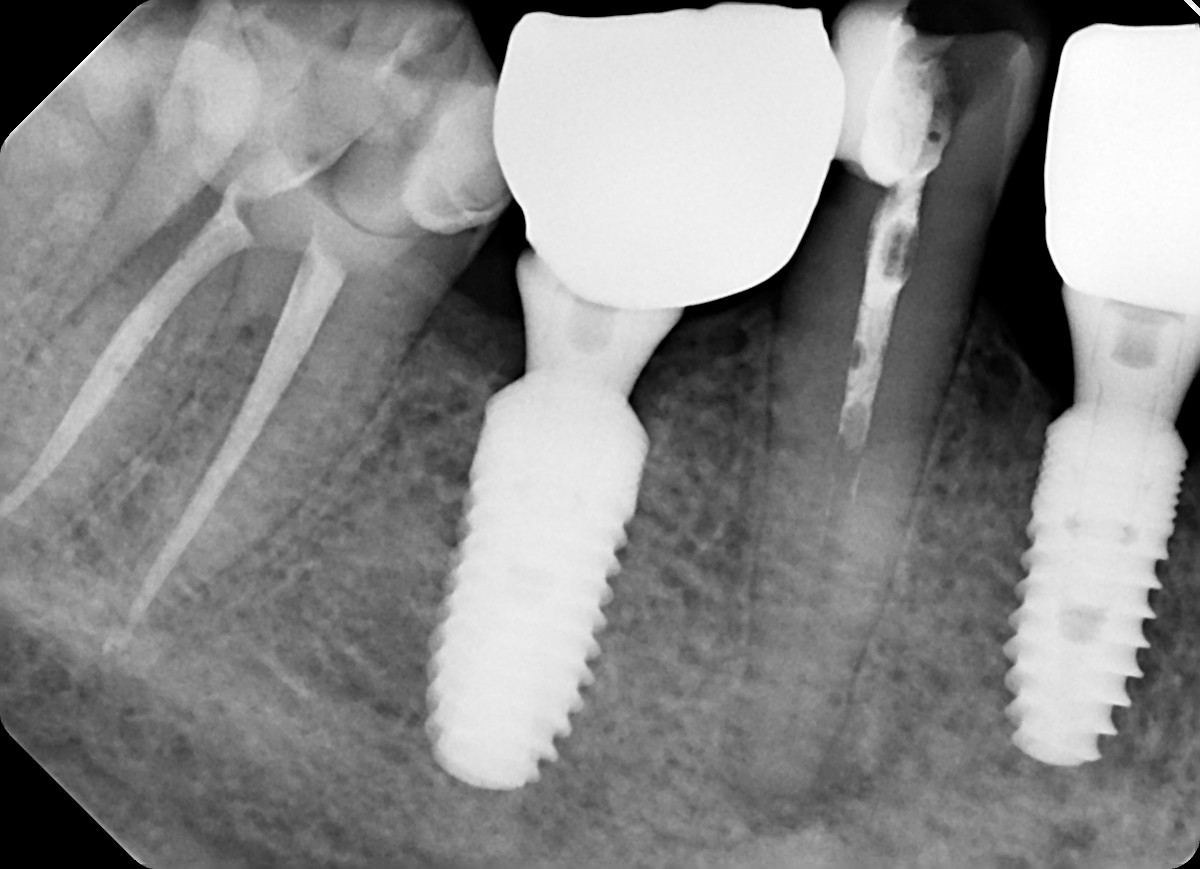

11. What option can be selected for root canal treatment of the tooth #3.6?

12. What option can be selected for root canal treatment of the tooth #3.7?